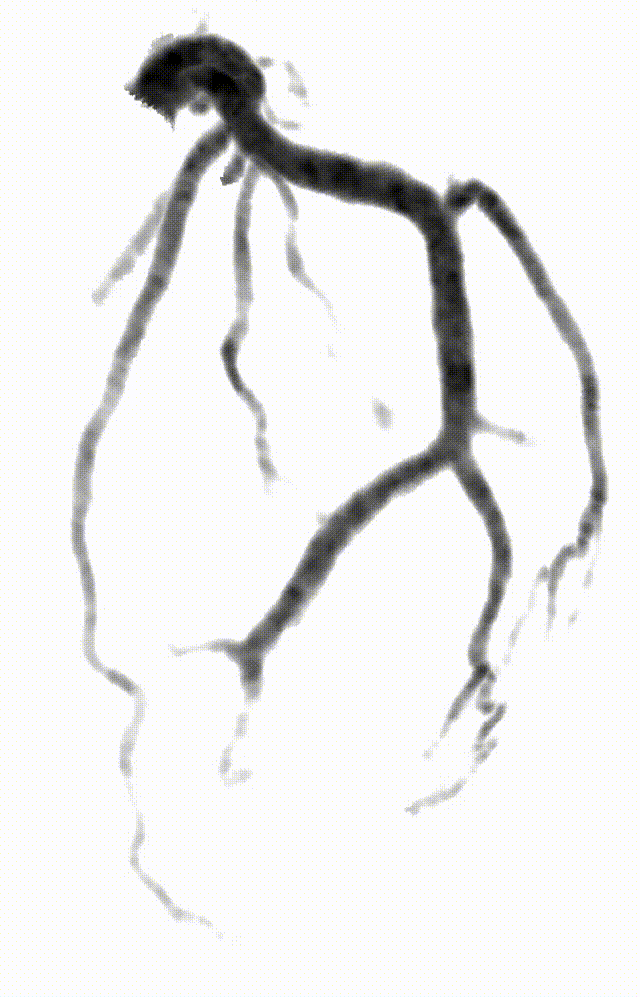

有请诸位且看此图像为何?

什么是联影ct真香预警?联影医疗双宽体双源CT大揭秘!TA竟然可以看到心脏的高清运动!_https://www.jmylbn.com_新闻资讯_第3张

您觉得该图是?点击选项前小圆圈答题:

DSA

CT

MR

X线摄影

您道此乃DSA?列位莫急,暂容小编卖个关子,且看下一图!

上述二图,皆出自同一人、同一种、同一次检查图像,乃冠脉CTA图像

基于这些突破,uCT SiriuX给我们带来了很多惊喜,文中开头所展示的冠脉CTA生成类DSA、类MR图像功能只是冰山一角,让我们进一步了解该设备在医院的实际临床应用及图像质量。

传统CT通常只能提供单时相静态结构成像,但uCT SiriuX打破了局限,可提供全心动周期多个时相的清晰结构成像信息,动态展示心脏结构运动变化,达到了类DSA、类MR的效果。